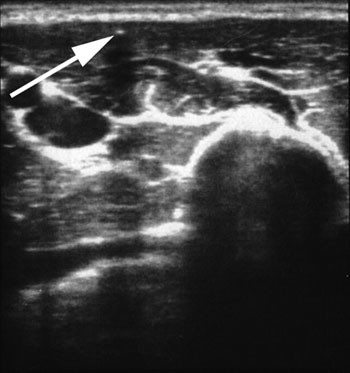

Implantatet er ikke røntgentett. Lokalisering av ikke-palpable implantater må gjøres med MR-undersøkelse eller høyfrekvent ultralyd (12) – (14). Mansour og medarbeidere anbefaler bruk av et lineært lydhode med 12 – 15 MHz som ideelt (12). I denne studien er det brukt et 11 MHz lydhode. Dersom det er usikkerhet om hvorvidt implantatet befinner seg i kroppen, bør det først utføres etonogestrelanalyse i serum (14). En slik analyse tilbys kostnadsfritt av produsenten. Slik analyse ble foretatt før pasienten ble henvist i de tilfellene der det var tvil om implantatet i det hele tatt var satt inn. Ved bruk av ultralyd vises implantatet best i tverrsnitt som en hvit prikk som kaster en skygge ned i underliggende vev (fig 3). Når implantatet er lokalisert, tegner man posisjonen med tusj på huden. Deretter legges i lokalanestesi et longitudinalt snitt på 1 – 3 cm, og man dissekerer seg så forsiktig ned i vevet til implantatet er lokalisert. Unngå kontakt med nerver og kar. Implantatet fjernes med en arteriepinsett. Avslutningsvis sys det med resorberbar tråd, om mulig intrakutant.